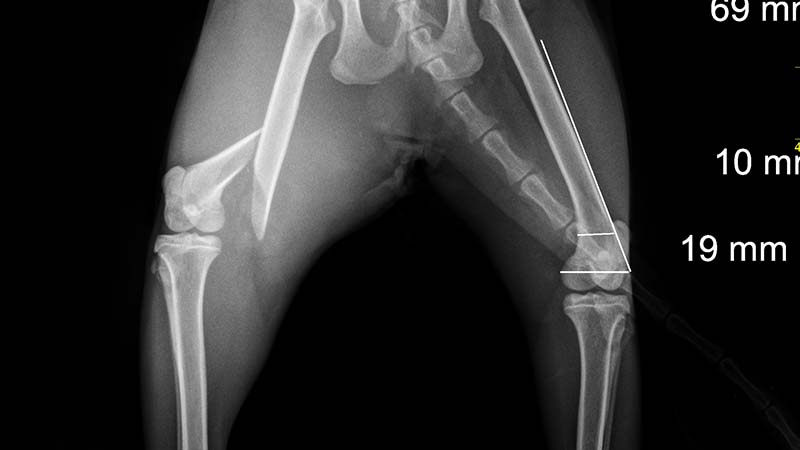

est la spécialité qui s’intéresse à l’appareil locomoteur et à ses affections. Elle comprend le diagnostic et le traitement chirurgical des lésions orthopédiques qui sont très diverses : fractures, ruptures et affections tendineuses, luxations, affections articulaires telle que l’ostéochondrose…

Le Dr Stéphane Daquin est diplômé du Certificat d’Etudes Spécialisées en traumatologie ostéo-articulaire et orthopédie animale. Il est responsable de l’orthopédie et du pôle chirurgical à la clinique. Il vous proposera, selon l’affection et l’animal, différentes techniques de réparation chirurgicale dont arthroscopie, correction de rupture de ligament croisé par la technique de TPLO, correction des fractures par voie minimale invasive… Il vous apportera son expertise sur les problèmes locomoteurs.